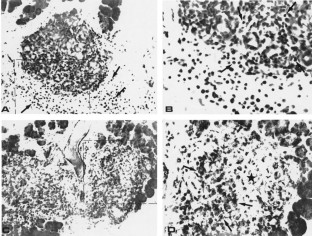

Figure 2